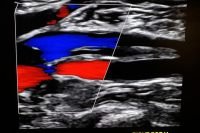

thrombosis ultrasound